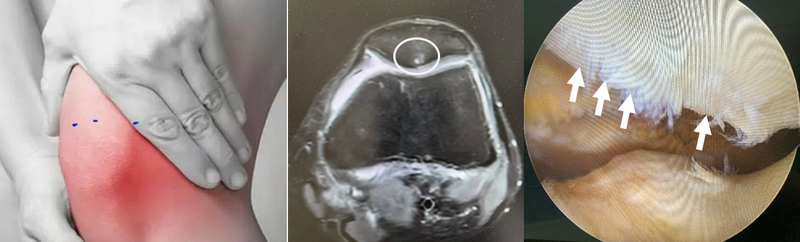

1、髌骨软骨是覆盖在髌骨后表面,与股骨(大腿骨)接触面的光滑组织,起到缓冲和减少摩擦的作用。当软骨因过度使用、受力不均或损伤而变软、龟裂或磨损时,会导致疼痛和活动受限,称为髌骨软化。2.常见原因过度使用:长期跑步、跳跃、深蹲等重复性膝关节活动。肌肉失衡:多见于大腿前侧股四头肌力量不足或内外侧肌力不均,导致屈伸膝关节时髌骨轨迹异常。膝关节的外伤:直接撞击或扭伤。先天因素:髌骨位置偏高,屈曲膝关节对髌骨软骨的压力较高,或者其他先天髌骨股骨对应关系异常。肥胖以及缺乏运动。3.典型症状膝盖前方疼痛:上下楼梯、深蹲、久坐后站立时加重。正常行走时有突然打软腿的情况。摩擦感:屈伸膝盖时可能有“沙沙”感或响声,伸直膝关节时把手放在髌骨上方可以感觉摩擦音。4.诊断医生通过询问病史多数可以诊断,想进一步了解髌骨软化的情况,需要行膝关节核磁检查。5.治疗早期较轻的髌骨软化可以通过股四头肌锻炼,养成良好生活习惯(避免爬楼深蹲动作)。通过肌肉锻炼和休养的方法效果不佳,可以注射玻璃酸钠或者PRP(富血小板血浆),配合非甾体类消炎止痛药物,附加康复锻炼和适当休养。极少需要手术,如果以上方案治疗半年仍效果不佳,MRI提示大面积软骨剥脱,或者出现髌骨的明显撞击,建议关节镜下手术治疗。6.预防措施科学运动:运动前热身,避免突然增加强度。强化肌力:均衡锻炼大腿、臀部和核心肌群。控制体重:减轻膝关节压力。正确姿势:避免长时间屈膝、跪姿或翘二郎腿。选择合适鞋子:运动时穿缓冲良好的鞋,避免穿高跟鞋久行。这就是髌骨髌骨软化,你了解了吗,养成良好生活习惯,早期发现轻微的髌骨软化,生活上干预,你就不会收到髌骨软化的困扰。

髌骨软化

如果走平地时膝关节不痛,上下楼梯的时候痛,或者蹲下站起来的时候膝关节痛,需要排除有没有髌骨软化症。髌骨表面覆盖的是透明软骨,仅有几毫米厚。如果因为急慢性损伤,软骨出现肿胀、龟裂、破碎等改变,叫做髌骨软化症。严重的时候软骨下的骨组织也会受累。诊断需要进行磁共振检查。x线和CT都无法观察到软骨。如果诊断有髌骨软化,需要避免引起膝关节疼痛的动作和活动,理疗有助于恢复。

一、什么是髌骨软化症?髌骨软化症(ChondromalaciaPatellae)并非字面意义上的骨头“变软”,而是指髌骨(膝盖骨)后方的软骨因慢性磨损或损伤而发生退行性改变。该病症的特点是软骨表面变得粗糙、软化甚至剥脱,导致膝关节活动时产生疼痛和摩擦感。髌骨软化症常见于长期运动人群、青少年运动员以及久坐办公族等。高风险人群包括:跑步、跳跃类运动爱好者(如篮球、羽毛球等);久坐后突然进行剧烈运动者;女性(因骨盆较宽,易引发髌骨轨迹异常);需要注意的是,髌骨软化症并非由于“缺钙”或“骨质疏松”引起,而是由于软骨代谢失衡所致。二、警惕这些症状:你可能中招了!1.上下楼梯痛:尤其是上楼梯时膝盖前方刺痛。2.久坐站起时卡顿感:俗称“电影院征”(长时间屈膝后站起困难)。3.蹲起或爬山时疼痛加剧。4.膝盖摩擦音:屈伸膝关节时出现“沙沙”声。三、保守治疗:抓住黄金修复期原则:早期干预可逆转损伤,避免进展为骨关节炎。1.疼痛管理:药物:短期使用非甾体抗炎药(如塞来昔布)缓解急性疼痛,但需警惕胃肠道副作用。外用贴剂:止痛贴膏联合局部冰敷(每次15分钟,每日2次)。2.护具与支具:髌骨稳定绑带:调整髌骨轨迹,适合运动时佩戴(如髌骨加压带)。肌内效贴扎:由康复师指导贴扎,辅助纠正髌骨偏移。3.生活方式调整:避免诱因:减少爬楼梯、深蹲、跪姿活动。体重管理:BMI每降低1,膝关节负荷减少4倍!四、康复治疗:重塑膝关节力学平衡核心理念:强化股四头肌内侧头(VMO)和臀肌,纠正髌骨轨迹异常。1.股四头肌等长收缩:仰卧位,膝下垫毛巾,用力下压保持5秒,20次/组,每日3组。2.踝泵训练:预防下肢静脉血栓,尤其适用于制动期。3.靠墙静蹲:背部贴墙,屈膝30°-45°(避免超过脚尖),保持至力竭,每日3组。4.蚌式开合:侧卧屈膝,弹力带抗阻抬膝,强化臀中肌(髌骨稳定的关键)。5.单腿闭链训练:站于平衡垫上,微屈膝保持稳定,每次1分钟。五、预防胜于治疗:1.运动防护:运动前动态拉伸股四头肌、腘绳肌。选择缓震跑鞋(如前后掌落差≤8mm),减少髌骨冲击。2.办公族贴士:每坐1小时起身活动5分钟,避免髌股关节长时间受压。3.女性专属建议:穿高跟鞋不超过2小时,避免加重髌骨前倾。七、何时需要手术?当保守治疗6个月无效、软骨剥脱严重(Outerbridge分级III-IV级)时,可考虑关节镜下软骨修复术或胫骨结节移位术,但需严格评估适应症。髌骨软化症是“预警信号”而非“绝症”。通过科学的阶梯治疗和持之以恒的康复锻炼,90%患者可显著改善症状。膝关节的寿命,取决于如何正确使用它!

您是否有遇到过这种情况:在您上下楼时、从椅子上或蹲下站起来的时候膝关节前方疼痛?如果是,那您可能就遇到了膝关节最常见的疾病之一:髌骨软骨软化和髌骨关节炎。之所以将这两个疾病放在一起,是因为他们是同一个疾病的不同阶段。髌骨软骨软化 在膝关节运动时,髌骨在股骨滑车的凹槽内滑动,就像小孩子在滑滑梯。髌骨的表面有一层软骨,保证其在滑动时十分顺滑。然而在某些情况下,比如内外侧肌肉力量不均衡,股骨髁发育异常,髌骨发育异常等,髌骨的平衡受到破坏。本来是全关节面受力变成了一侧关节受力,就好像人本来两条腿走路,由于某种原因现在只能一条腿走路。所有的压力都集中在了一侧,压强变大,局部的髌骨就会缺血坏死和脱落。在早期,髌骨仅表现出软骨水肿,轻度损伤、软骨下骨水肿和囊肿等情况,我们称为髌骨软骨软化。随着病情的进一步发展,软骨逐渐碎裂、崩解脱落,软骨下的骨质开始继发性的增生、硬化、骨赘生成,同时导致股骨髁的进一步损伤,病情便转向了髌股关节炎。引自:https://adrianoleonardi.com.br/artigos/tag/cirurgia-da-condromalacia-patelar/髌骨关节炎 髌股关节炎是髌骨和股骨之间关节的退变,主要表现为软骨的不同程度损伤、剥脱,骨赘生成。髌骨软骨软化是髌股关节炎的主要原因之一,当然还有其他的诱因,比如外伤、半月板退变、膝关节力线异常、其他膝关节间室的骨关节炎累及等。此外还要注意,因为膝关节软骨是靠关节内压力波动将关节液挤入软骨内供应营养,因此久站久坐是膝关节各个间室骨关节炎的重要诱因。引自:https://orthoinfo.aaos.org/en/diseases--conditions/patellofemoral-arthritis/非手术治疗 通过合适和正规的治疗,髌骨软骨软化和早期的髌骨关节炎是可以得到缓解和治愈的。前提是你需要找到专业的医生进行合适的诊断,找到病因并对症治疗。非手术治疗可以缓解一大部分的患者:1. 如果体重过大,需要尽快的减重。减重可以显著的恢复膝关节内的各种不适感。2. 如果有结构上的问题,例如股骨髁发育不良、髌骨脱位等情况,需要医生评估,必要时手术治疗。3. 出现症状后需要休息2周,避免负重情况下的屈膝,减少髌骨关节的压力,使软骨得到一定的恢复,但期间需要在床上进行膝关节周围肌肉的锻炼。待症状缓解后开始逐渐恢复负重,加强膝关节周围肌肉及小肌群的锻炼,但避免过度负重。4. 补充多种维生素有利于软骨的营养。尽管有些研究认为硫酸软骨素和氨基葡萄糖对膝关节软骨保护作用甚微,但笔者认为仍然可以尝试。5. 如果症状十分严重,可考虑NSAIDs类抗炎止疼药。其可以缓解一部分的症状,但其可能不利于软骨的修复。6. 关节内注射激素和玻璃酸钠,在一定程度上可以缓解症状,但不宜多次反复进行。一定注意要到正规的医疗机构进行注射,严格的预防感染。 可参考一下康复计划,请在医生指导下进行:手术治疗 在非手术治疗效果不佳的情况下,可以考虑手术治疗。对于无明显力线不良的早中期患者,可以考虑微创关节镜下进行关节内的清理、髌周去神经化和软组织平衡手术。如果软骨损伤较重,不伴明显的关节炎,我们还可以通过骨髓刺激、软骨移植等手术方式进行软骨的修复。对于伴有明显力线异常、髌骨脱位的患者,我们还需要进行力线的矫正手术。最后,对于晚期严重的骨关节炎、合并其他间室的关节炎,我们可以进行关节置换术。